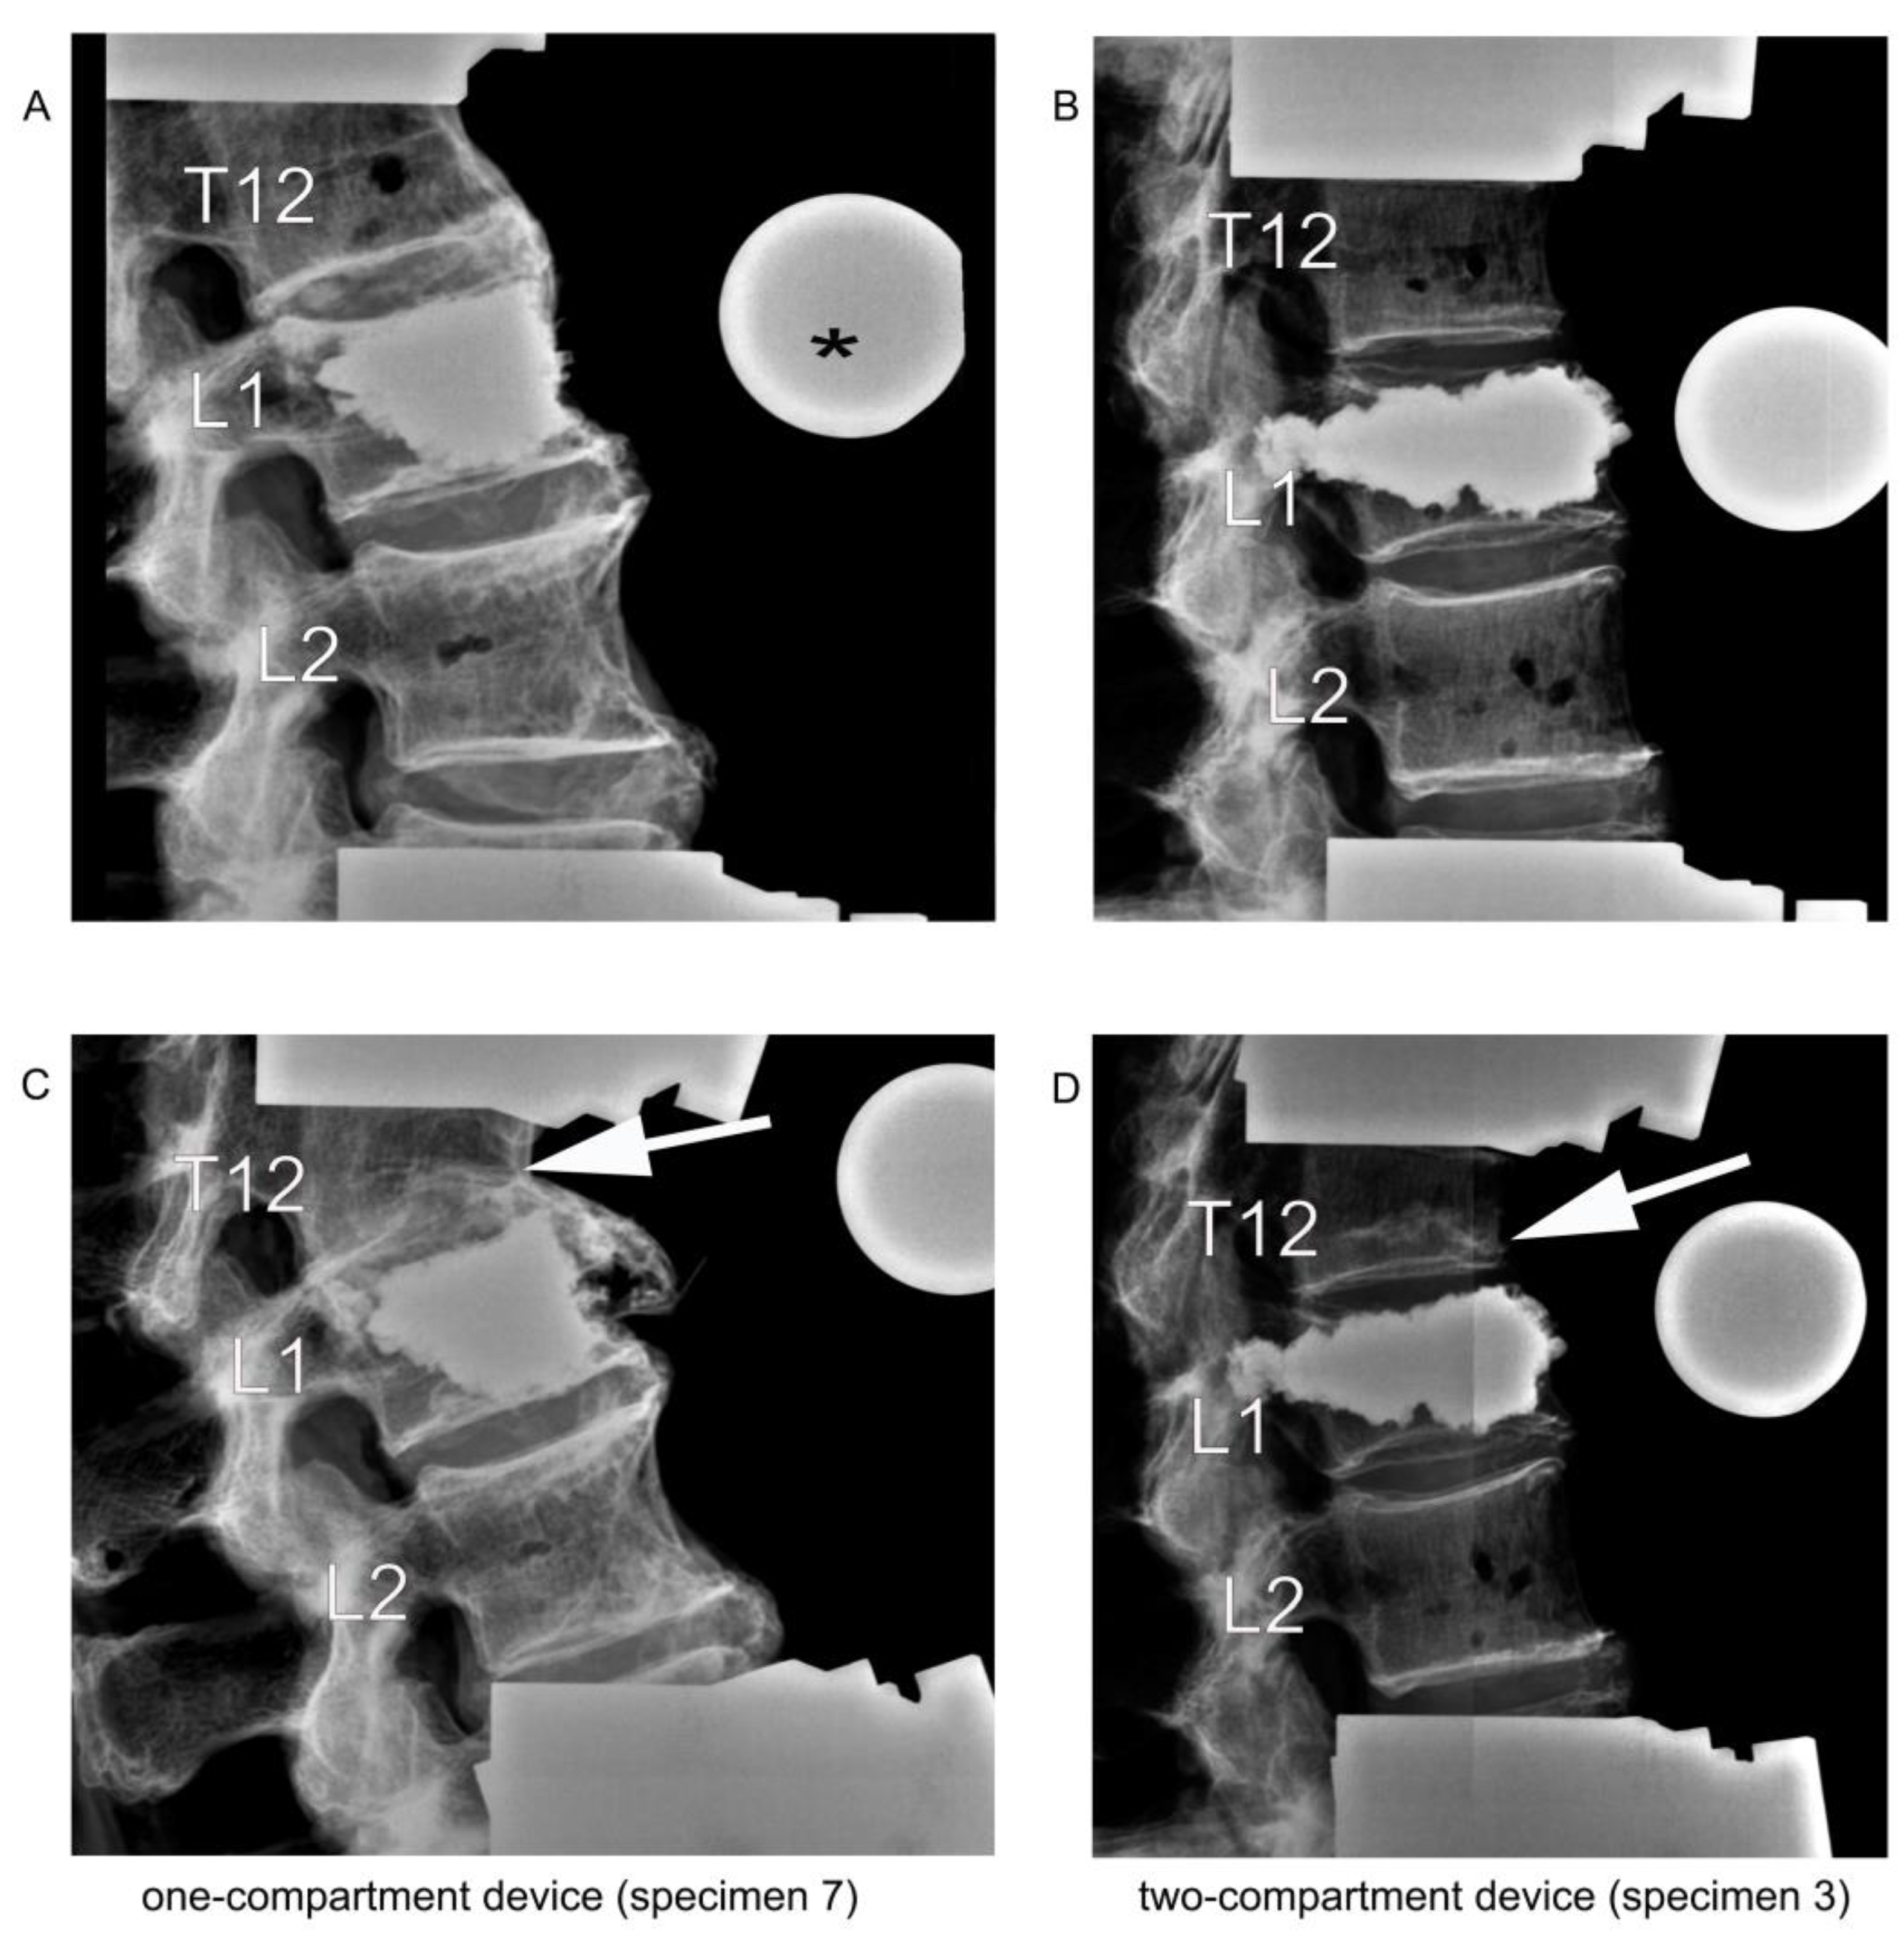

Figure 7.

Lateral radiographic images upon kyphoplasty of L1 (A,B) and after adjacent fracture of T12 (C,D) resulting from the cyclic loading test of load-bearing capacity. The asterisk (*) in (A) refers to the radiographic reference ball. The arrows in (C,D) point to the fractured T12.